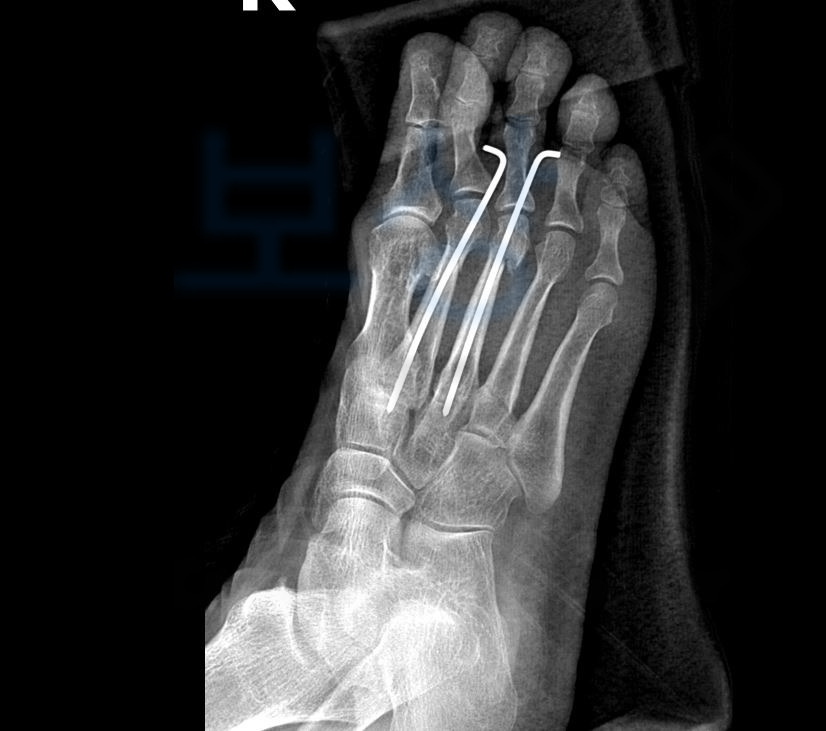

김@@님은 과거 손목 골절을 당하셨고 최근 복사의 골절 진단도 받아 두 부위 모두 금속으로 고정 수술을 받으셨습니다.

발목 관절의 약간의 장해 5%